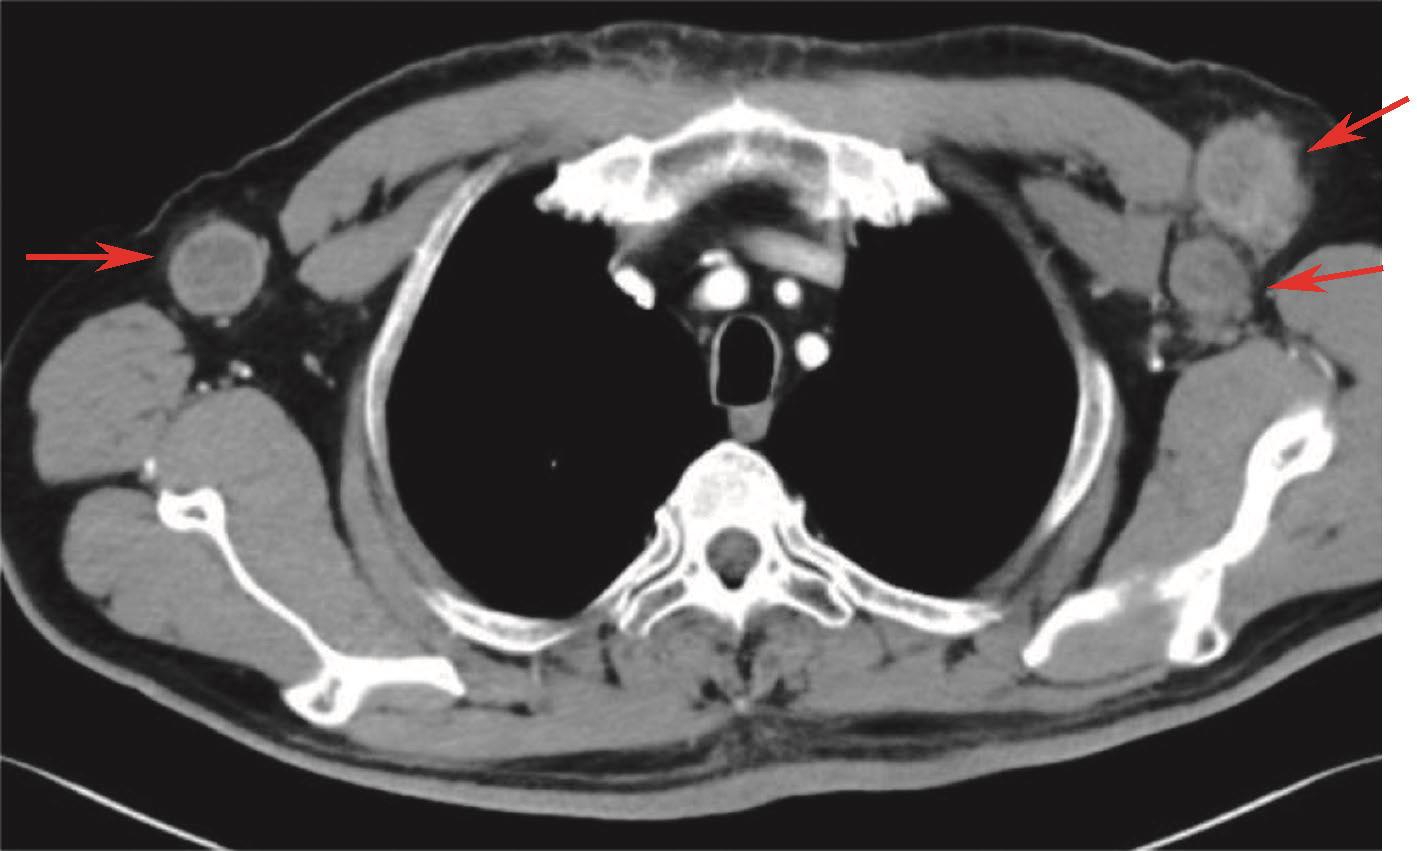

入院后完善基线检查,2015-11-04完善颈部增强CT及MRI检查:下咽部治疗后改变,双侧颈部、左锁骨上淋巴结肿大(图2)。胸腹盆增强CT示双肺多发小结节(图3)。

图2 颈部增强MRI(基线)

注:提示左锁骨上、颈部多发淋巴结(箭头指示为靶病灶)。